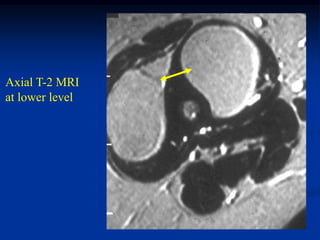

Case #1211.3                        Synovial hemangioma knee

68 year old female with soft mass medial knee for years

Cor T-1    T-2

Gad

Sag PD   Gad

Axial T-2   Gad